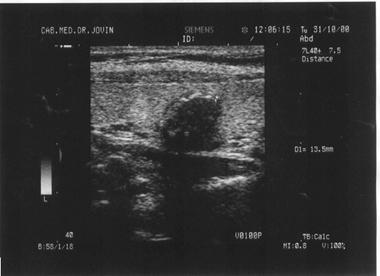

Spatiul fizic de separare dintre structuri sau tesuturi cu densitati diferite (respectiv impedante acustice diferite) se numeste interfata. Interfata este cu atat mai evidenta cu cat diferenta dintre densitatea tisulara este mai mare. De exemplu, limita de separatie intre chiste si tesuturile solide invecinate este foarte evidenta; de aceea chisturile din interiorul unui parenchim sunt vizibile ecografic chiar la dimensiuni mici. Foto I 62 (chist).

Cu cat diferenta dintre densitatea tesuturilor este mai mica, cu atat interfata dintre acestea apare mai putin distinct pe ecranul ecografului. De exemplu, un nodul parenchimatos cu densitate identica cu aceea ce inaparent ecografic chiar la dimensiuni mari. Fig 83 b, pag. 72 Badea.